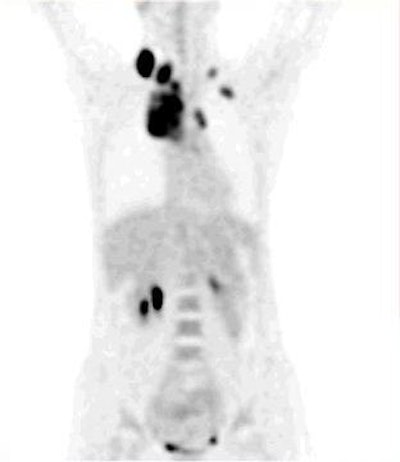

![]() |

| Fig. 4. Whole-body FDG-PET projection images of a patient with a lymphoma reveal great detail about various structures included in the field of view. The high quality of these images demonstrates a substantial improvement in PET instrumentation, which has further enhanced effective utilization of FDG in a multitude of malignant and nonmalignant disorders. |